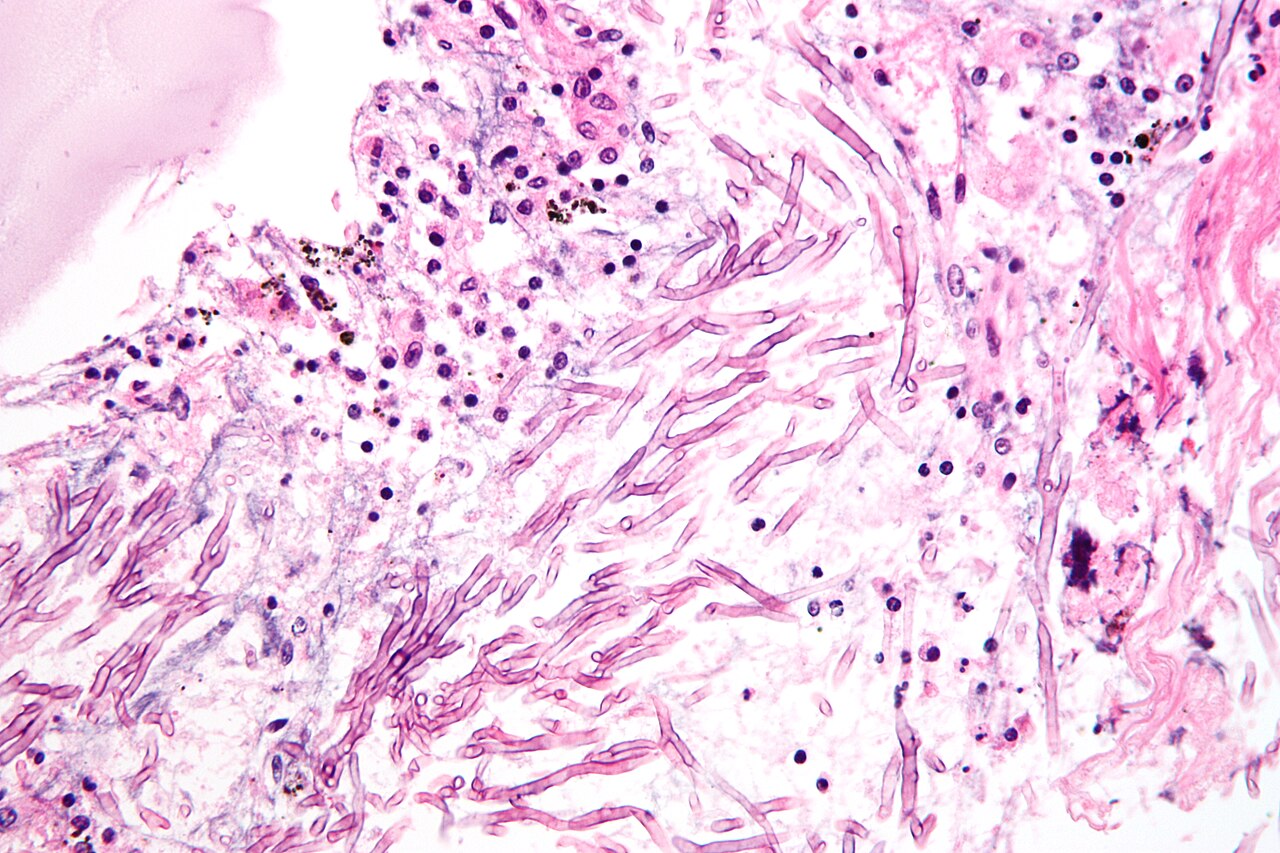

Fungal Diseases

Fungal infections are less common but can still be serious, especially in poorly managed environments.

The most well-known example is aspergillosis, which is caused by inhaling mold spores from damp bedding, spoiled feed, or poorly ventilated spaces.

These infections primarily affect the respiratory system and can be difficult to treat once established. Birds may show signs like labored breathing or gasping.

Aspergillosis

A respiratory disease caused by inhaling mold spores.

- Symptoms: Gasping, labored breathing, weakness

- Cause: Moldy bedding, feed, or poor ventilation

- Treatment: Difficult once established

- Prevention: Dry conditions and clean feed